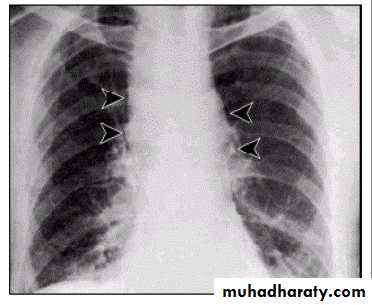

Mediastinal widening due to inhalational anthrax.

Mediastinal widening and pleural effusion on Chest X-Ray in inhalational anthrax